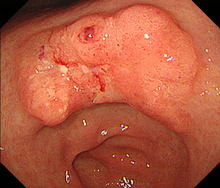

胃がんは、胃の壁の最も内側にある粘膜内の細胞が、何らかの原因でがん細胞になって無秩序に増殖を繰り返すことで生じます。胃がん検診などの検査で見つけられる大きさになるまでには、通常何年もかかるといわれています。胃がんの診断には胃の内側から内視鏡(胃カメラ)で観察することにより診断が可能であり、胃がんの部分がイボのように盛り上がったり、潰瘍を形成し陥凹している部分、色調の変化した部分などを詳しく観察します。生検検査でがん細胞を認めると診断が確定します。胃がんの内視鏡写真を提示します(図1)。